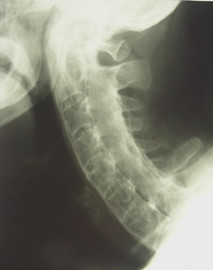

Badanie obrazowe przedstawia:

Pytanie 113